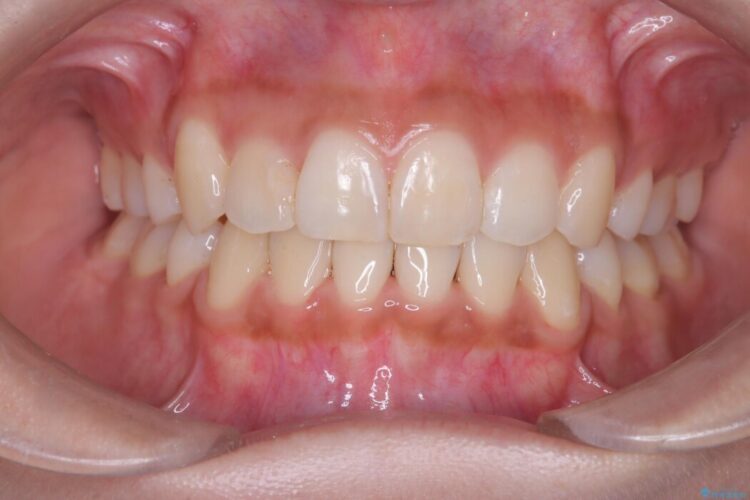

複雑に重なり合っていた前歯を、抜歯で作ったスペースを活用して丁寧に整列。単に並べるだけでなく、角度を1ミリ単位で調整しながら後ろへ下げることで、口元の突出感をスッキリ解消しました。

理想のEラインと、ガタつきのない美しい歯並びを同時に手に入れられました。